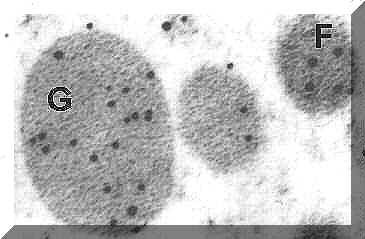

We began this work after we discovered that a subpopulation of GH cells expressed messenger ribonucleic acid (mRNA) for the beta subunits of gonadotropins just before ovulation. We used dual-labeling that detected mRNA for gonadotropins by in situ hybridization and growth hormone antigens by immunolabeling.

A photograph of a dual-labeled growth hormone cell is shown in this figure. The growth hormone cell (G) is labeled dark orange for growth hormone antigens. The cell also contains messenger RNA for one of the gonadotropins, follicle stimulating hormone. This is labeled dense gray-black (F) U=unlabeled cell. We suggest that it has become a transitional gonadotrope to augment the ovulatory surge of gonadotropins. Also see dual-labeled figures in the sidebar